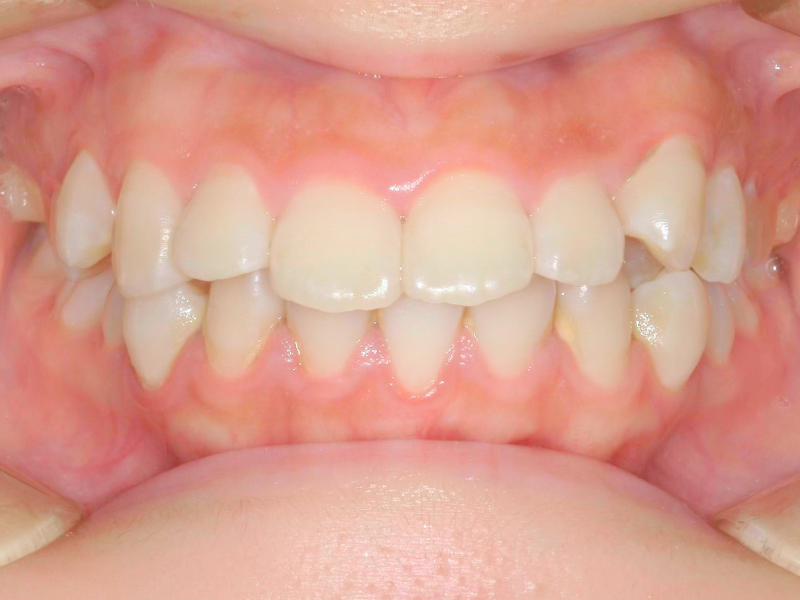

10代、女性、ワイヤー

| 施術内容 | 主訴:上下前歯でこぼこ。なるべく抜きたくない。 詳細:ワイヤー矯正での歯並び改善 詳細:ワイヤー矯正での歯並び改善 歯肉炎リスクあるため、今後は後戻りのチェックとともに歯肉炎管理もしていきます。 |

|---|---|

| 治療期間 | 12ヶ月(2/6現在 治療終了) |

| リスク・副作用 | ■リスク・副作用 ・治療の初期段階では、痛みや不快感が生じやすくなりますが、一週間前後で慣れます。 ・歯の動き方には個人差があるため、予想された治療期間より延長する場合があります。 |

| 費用 | ワイヤー矯正 60万円(税込660,000円) |